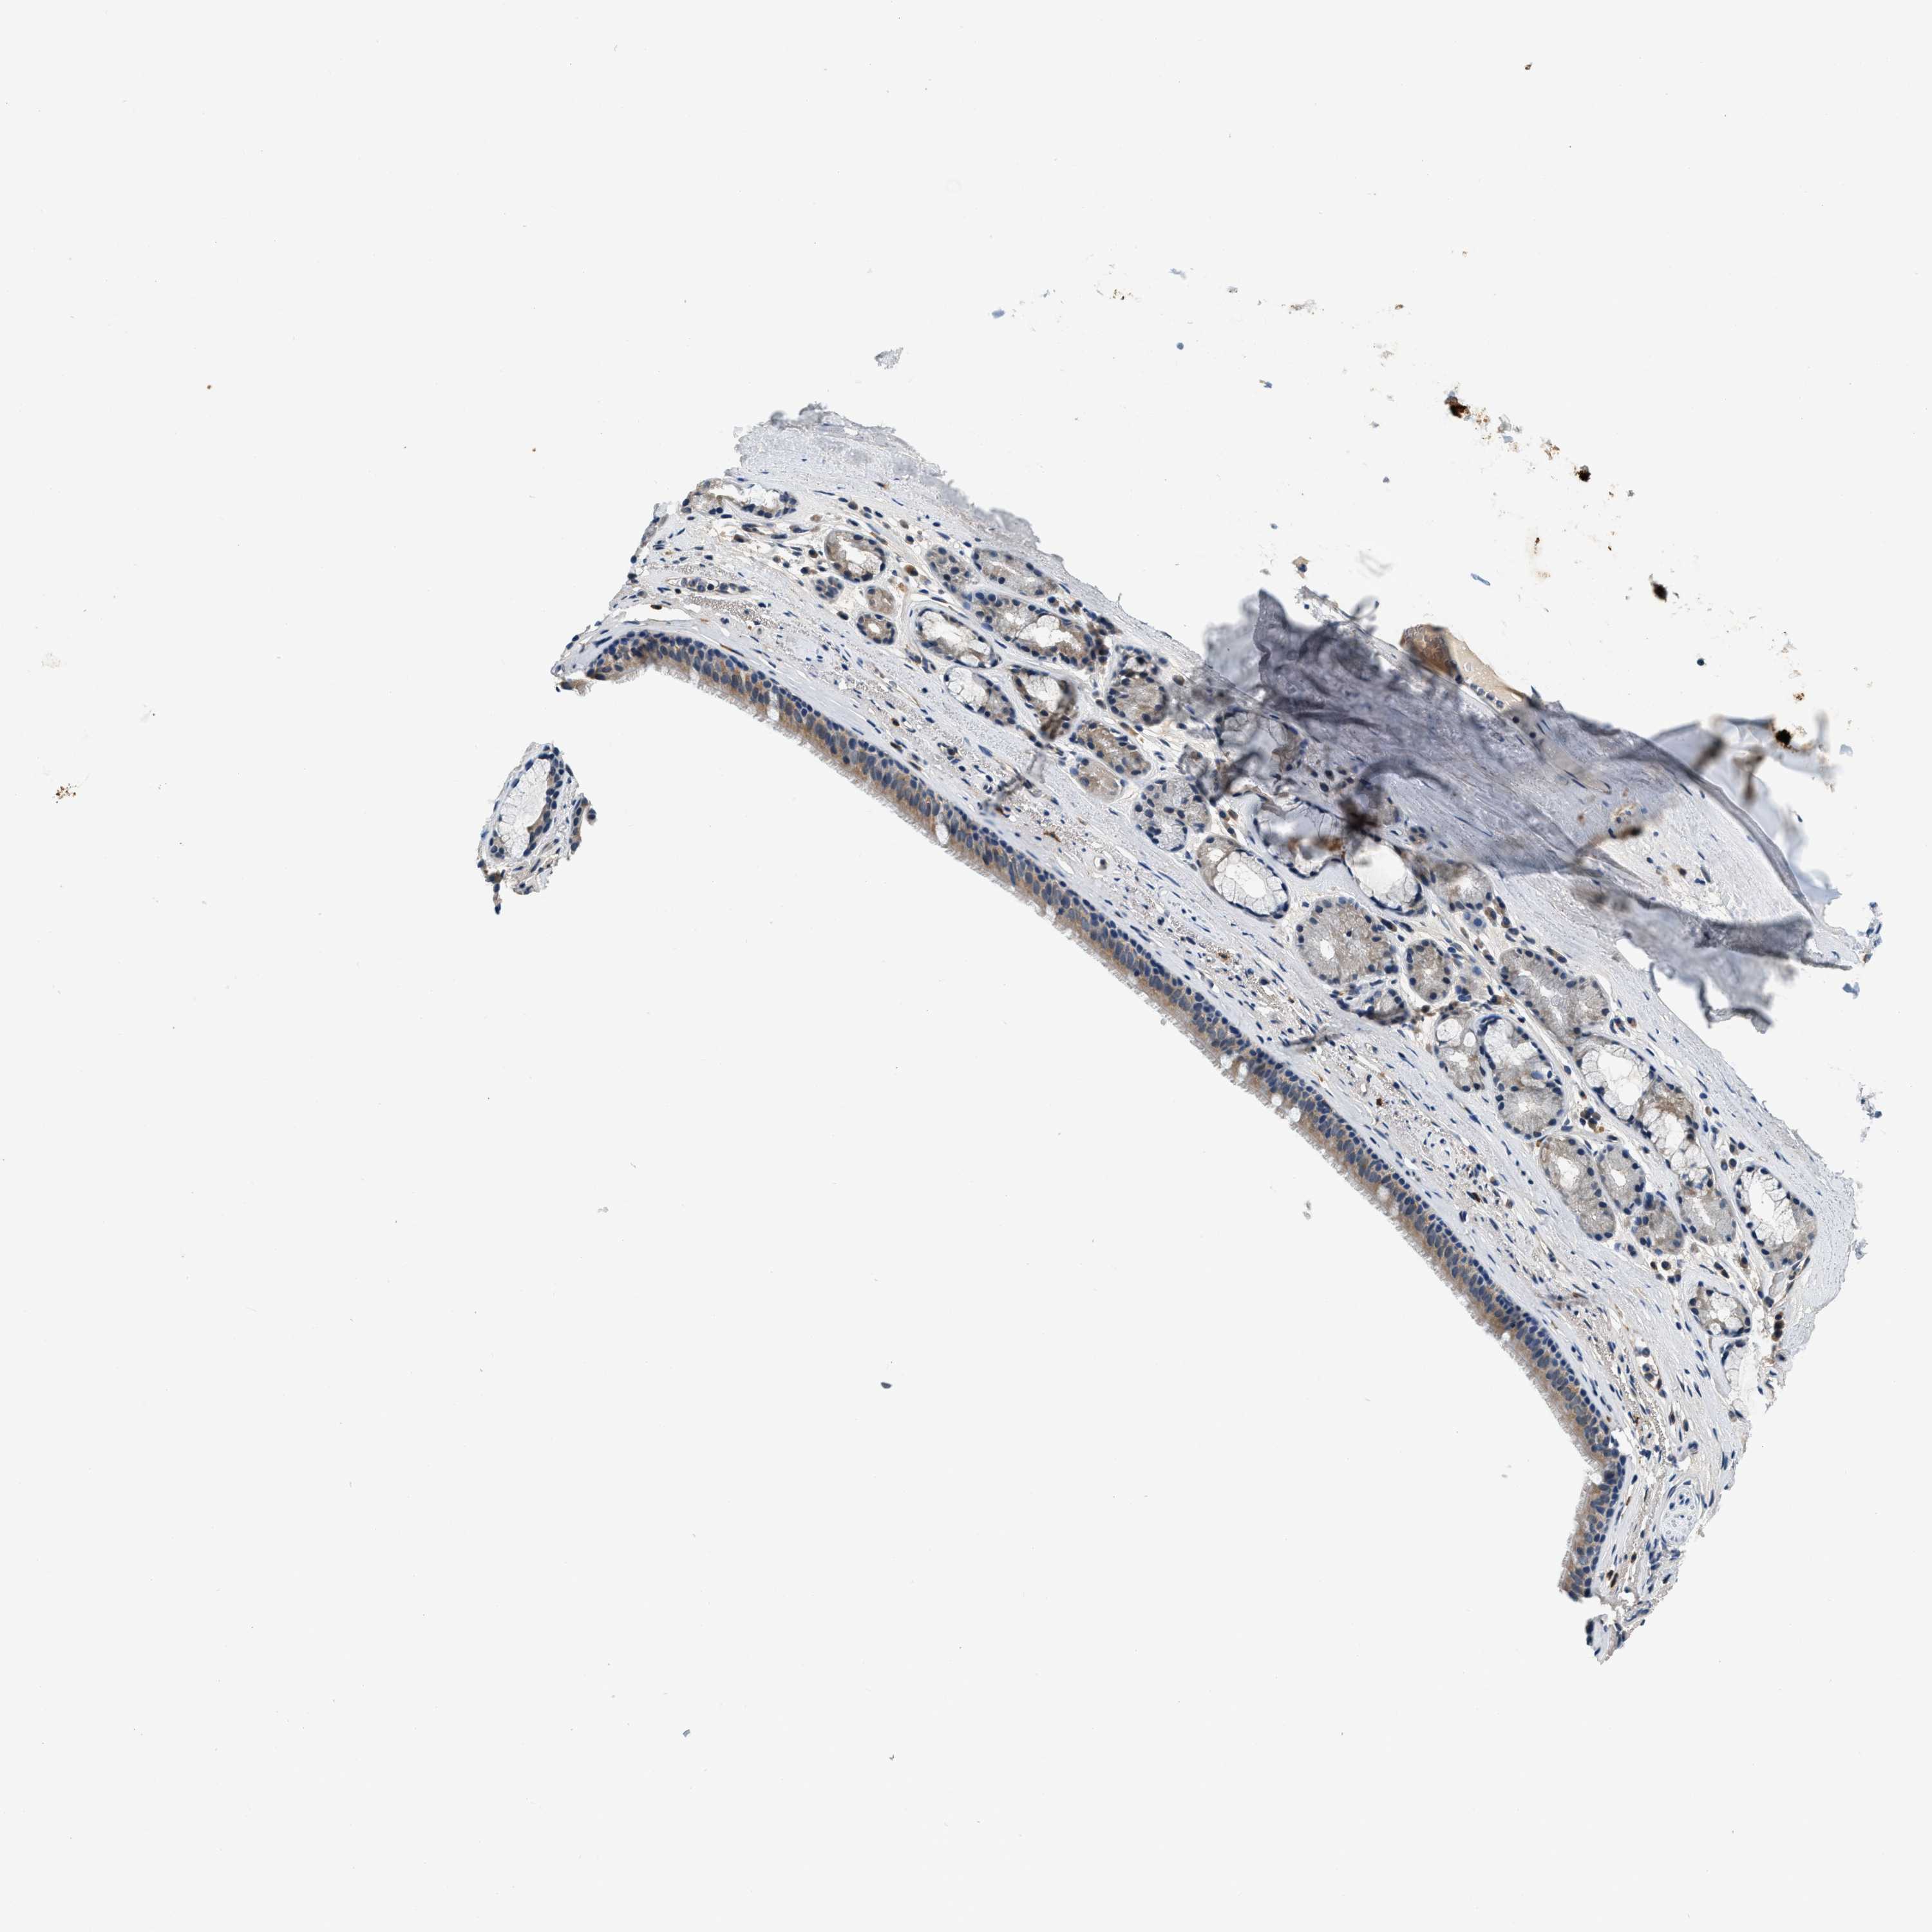

BRONCHUS - Antibody stainingi

Antibody staining in the annotated cell types in the current human tissue is reported as not detected, low, medium, or high, based on conventional immunohistochemistry profiling in selected tissues. This score is based on the combination of the staining intensity and fraction of stained cells.

Each image is clickable and will lead to virtual microscopy that enables deeper exploration of all samples and also displays staining intensity scores, fraction scores and subcellular localization as well as patient and tissue information for each sample.

Antibody HPA019226Antibody HPA031249

Respiratory epithelial cells MediumHigh